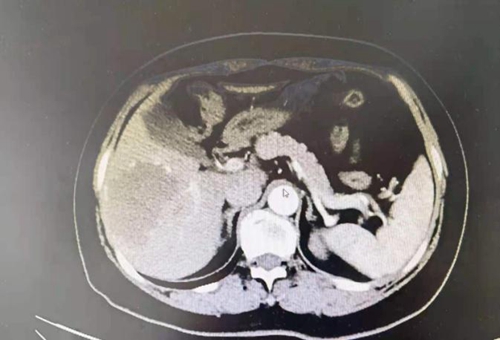

一個(gè)月前,59歲的張阿姨(化名)因?yàn)榧毙晕秆椎疆?dāng)?shù)蒯t(yī)院就診,CT檢查時(shí)發(fā)現(xiàn)自己右肝有85mm×70mm×50mm的腫瘤占位,急壞了一家人。

其中6,7段為肝臟右后葉

肝血管瘤是肝內(nèi)血管結(jié)構(gòu)發(fā)育異常所導(dǎo)致的良性腫瘤,多為海綿狀血管瘤。肝臟是人體腹腔內(nèi)最大的實(shí)質(zhì)性器官,組織結(jié)構(gòu)脆弱,血流豐富,而張阿姨的腫瘤位于特殊位置,一旦發(fā)生破裂,就有可能出現(xiàn)難以控制的大出血甚至危及生命。